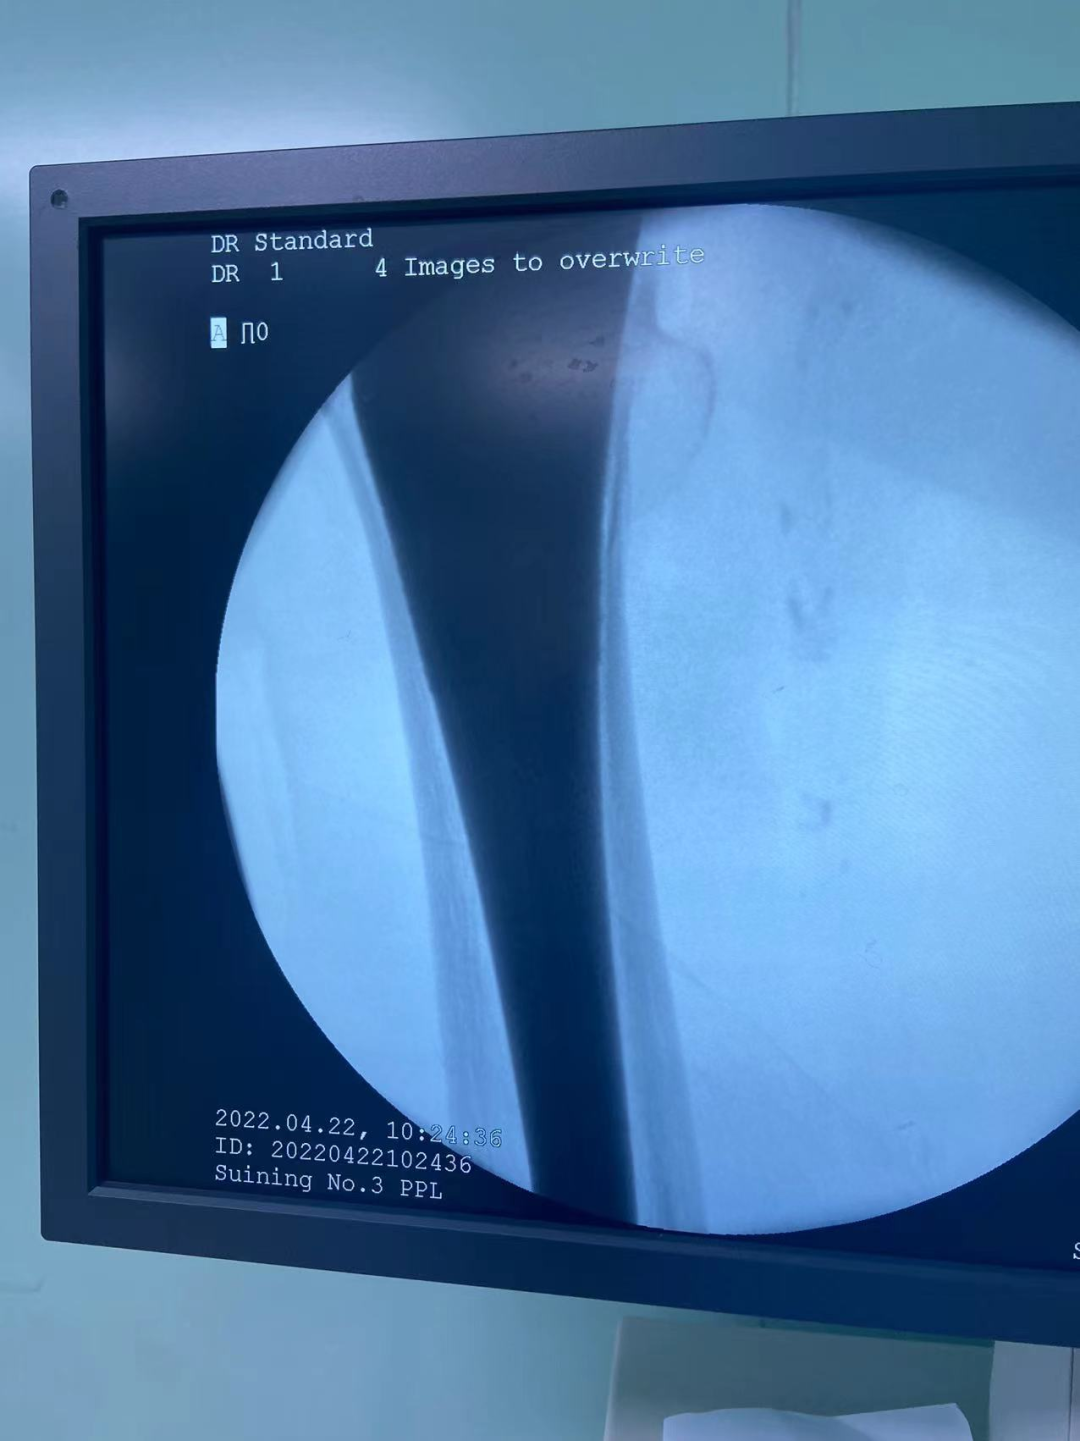

4月22日上午,历经30分钟,我院成功实施第一例执行国家集采人工关节置换手术,费用由之前的2.3万元左右降到7000元左右,患者为它付费少七成。

79岁何奶奶,因扭伤后出现右髋部疼痛伴活动受限3天入院,诊断为右股骨颈骨折、骨质疏松症,需要手术治疗,结合患者的基础疾病及年龄,经与患者及家属沟通,我院骨伤科团队决定为她实施人工股骨头置换术,恰好赶上国家政策—人工关节集中采购,人工关节降价!4月22日上午,由骨伤科周建全主任主刀,历时30分钟完成手术,术中失血仅50ml!

该名患者成为我院执行国家人工关节集中带量采购落地的首位获益患者,手术耗材费用仅7000元,比过去节省近70%,约1.6万元。耗材费用大幅降低成为关节伤患者的重大福音,进一步减轻了患者的就医负担。